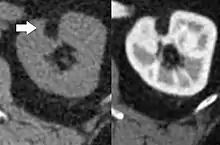

Three methods of scanning can detect angiomyolipomas: ultrasound, computed tomography (CT), and magnetic resonance imaging (MRI).[5] Ultrasound is standard and is particularly sensitive to the fat in angiomyolipomas, but less so to the solid components. However, accurate measurements are hard to make with ultrasound, particularly if the angiomyolipoma is near the surface of the kidney (grade III).[4] CT is very detailed and fast, and allows accurate measurement. However, it exposes the patient to radiation and the dangers that a contrast dye used to aid the scanning may itself harm the kidneys. MRI is safer than CT, but many patients (particularly those with the learning difficulties or behavioural problems found in tuberous sclerosis) require sedation or general anaesthesia, and the scan cannot be performed quickly.[3] Some other kidney tumours contain fat, so the presence of fat is not diagnostic. Distinguishing a fat-poor angiomyolipoma from a renal cell carcinoma (RCC) can be difficult.[6] Both minimal fat AMLs and 80% of the clear-cell type of RCCs display signal drop on an out-of-phase MRI sequence compared to in-phase.[7] Thus, a lesion growing at greater than 5 mm per year may warrant a biopsy for diagnosis.[3]